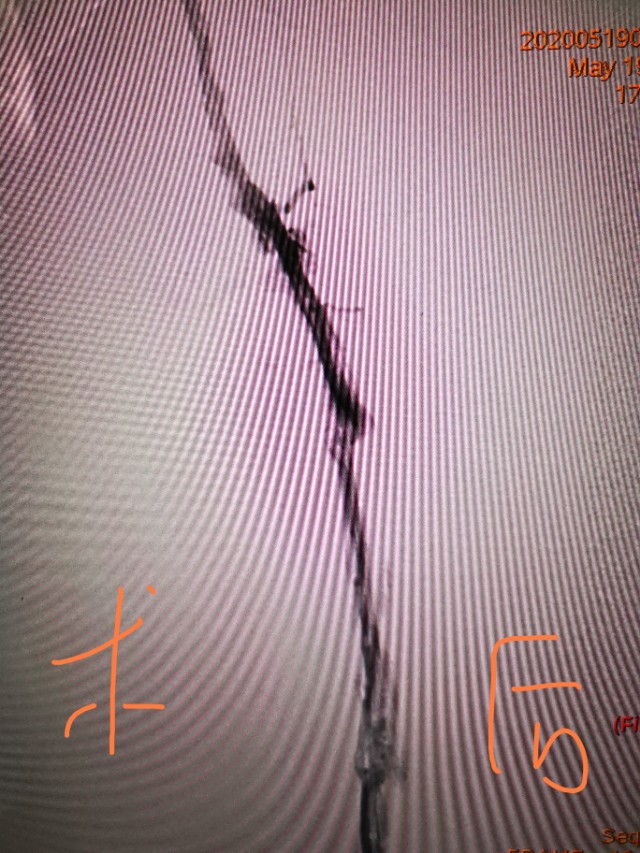

我们可以进行药物治疗和介入治疗,只要病人最近半年没有活动性出血如胃出血和脑出血,我们可以进行抗凝治疗。抗凝最大的风险是出血和血栓脱落,出血我们可以监测凝血时间,防治肺动脉栓塞,我们可以放滤器保护肺动脉。介入治疗主要是对有血栓的静脉进行血栓抽吸、球囊扩张、支架植入等。